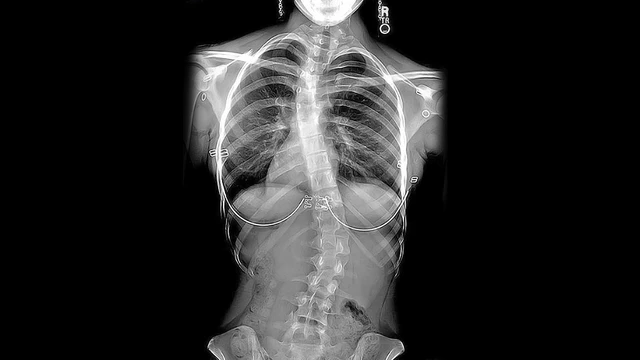

كيف يتم اكتشاف الجنف (اعوجاج العمود الفقري) مبكرًا؟

عادة يتم التشخيص من خلال:

- الفحص السريري للظهر

- الأشعة السينية للعمود الفقري

- متابعة الحوض وتوازن الجسم

- في بعض الحالات: تصوير متقدم لتقييم العظام